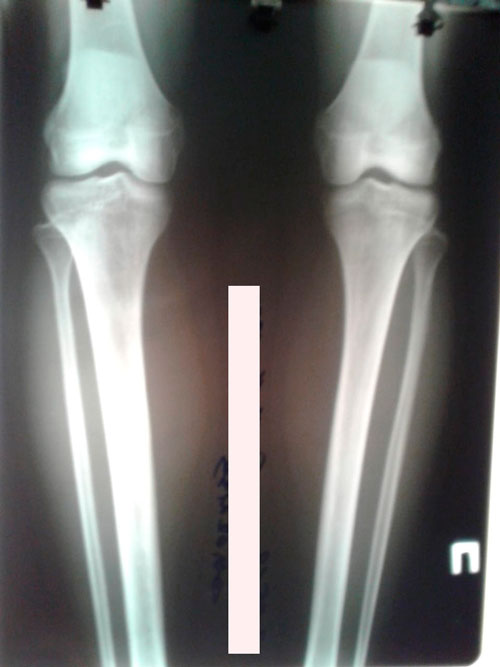

Дата операции - 08.05.2019г.

Дата снятия аппаратов -03.08.2019г.

Срок сращения - 85 дней.

рентген перед снятием аппаратов

IMG_4765-03-08-19-11-45.JPG

IMG_4764-03-08-19-11-45.JPG